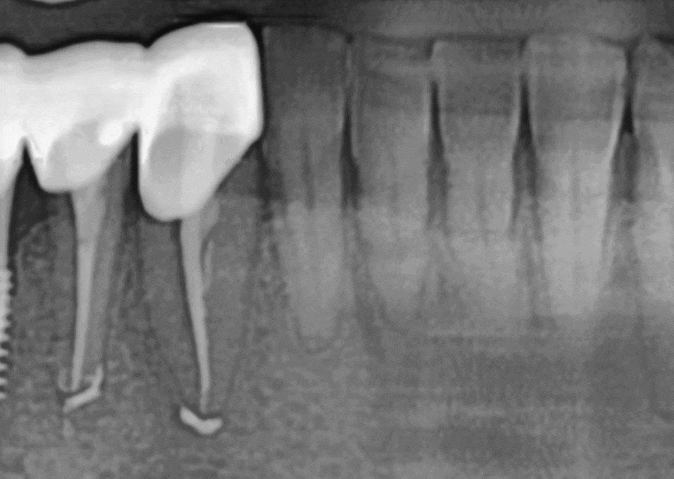

250121

조금 더 정밀한 사진 촬영을 해 보니 (ct) 상황은

예상보다 심각했습니다.

뿌리 사이에 염증이 깊숙이 퍼져 있었고,

치아를 지탱하는 주변 뼈가 이미 상당 부분 손실된 상태였습니다.

게다가 입천장의 절반 이상이 심하게 부어올랐고,

잇몸에서는 고름이 나오고 있었습니다.

하지만 포기하지 않고 복잡한 신경관들을

꼼꼼히 제거하고 소독하는 과정을 여러 차례 반복했습니다.

염증이 어느 정도 가라앉은 후

MTA라는 재료를 사용하여 뿌리 끝을 단단히 막아줍니다.

*MTA 적용 사례

사진이 뚜렷하게 잘 나온 다른 환자분 사진을 예시로 보여드리겠습니다.

뿌리 끝 염증 상태 (전)

치아 뿌리 염증 빼야 된다는 치아, 이렇게 살렸습니다. 치료 방법